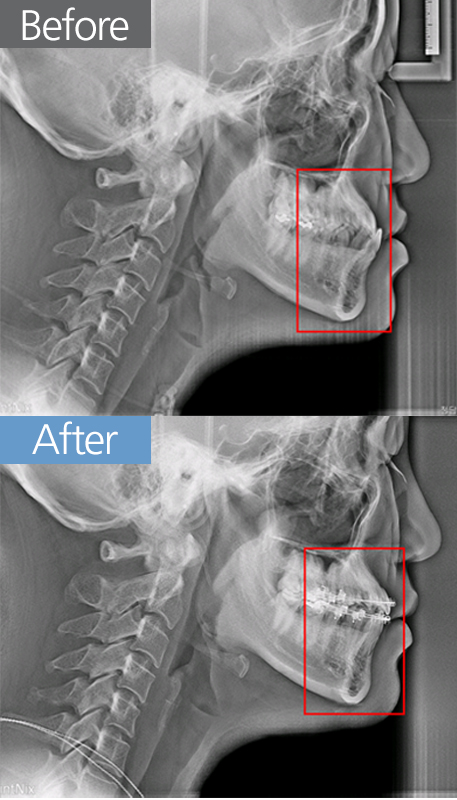

치아교정 반대교합 교정

반대교합 교정